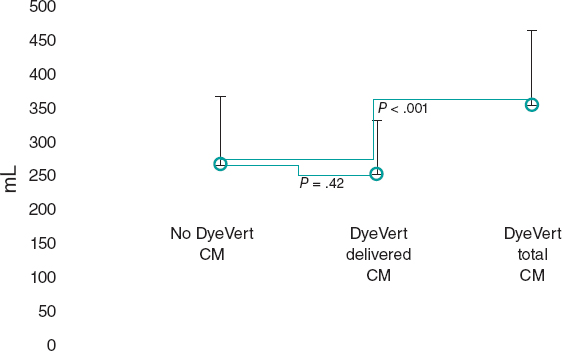

The macroscopic examination revealed an infarction region in the lateral side from apical to basal level. The use of triphenyltetrazolium chloride stain confirmed the occurrence of a transparietal infarction (figure 2) whose size is shown on table 1 of the supplementary data together with the weight of each level.

Figure 2. Animal #1. Presence of transparietal infarction areas from basal (A) to apical level (D). Triphenyltetrazolium chloride stain.

The macroscopic evaluation revealed the presence of a transparietal infarction region in the posterior side damaging the medium and basal segments (figure 3) and papillary muscle (figure 4). The spread of this lesion into the different levels is shown on table 2 of the supplementary data.

Figure 3. Animal #2. Presence of transparietal infarction areas from medium (B) to basal level (D). Triphenyltetrazolium chloride stain.

Figure 4. Papillary muscle lesion. Lower part of level C. Triphenyltetrazolium chloride stain.